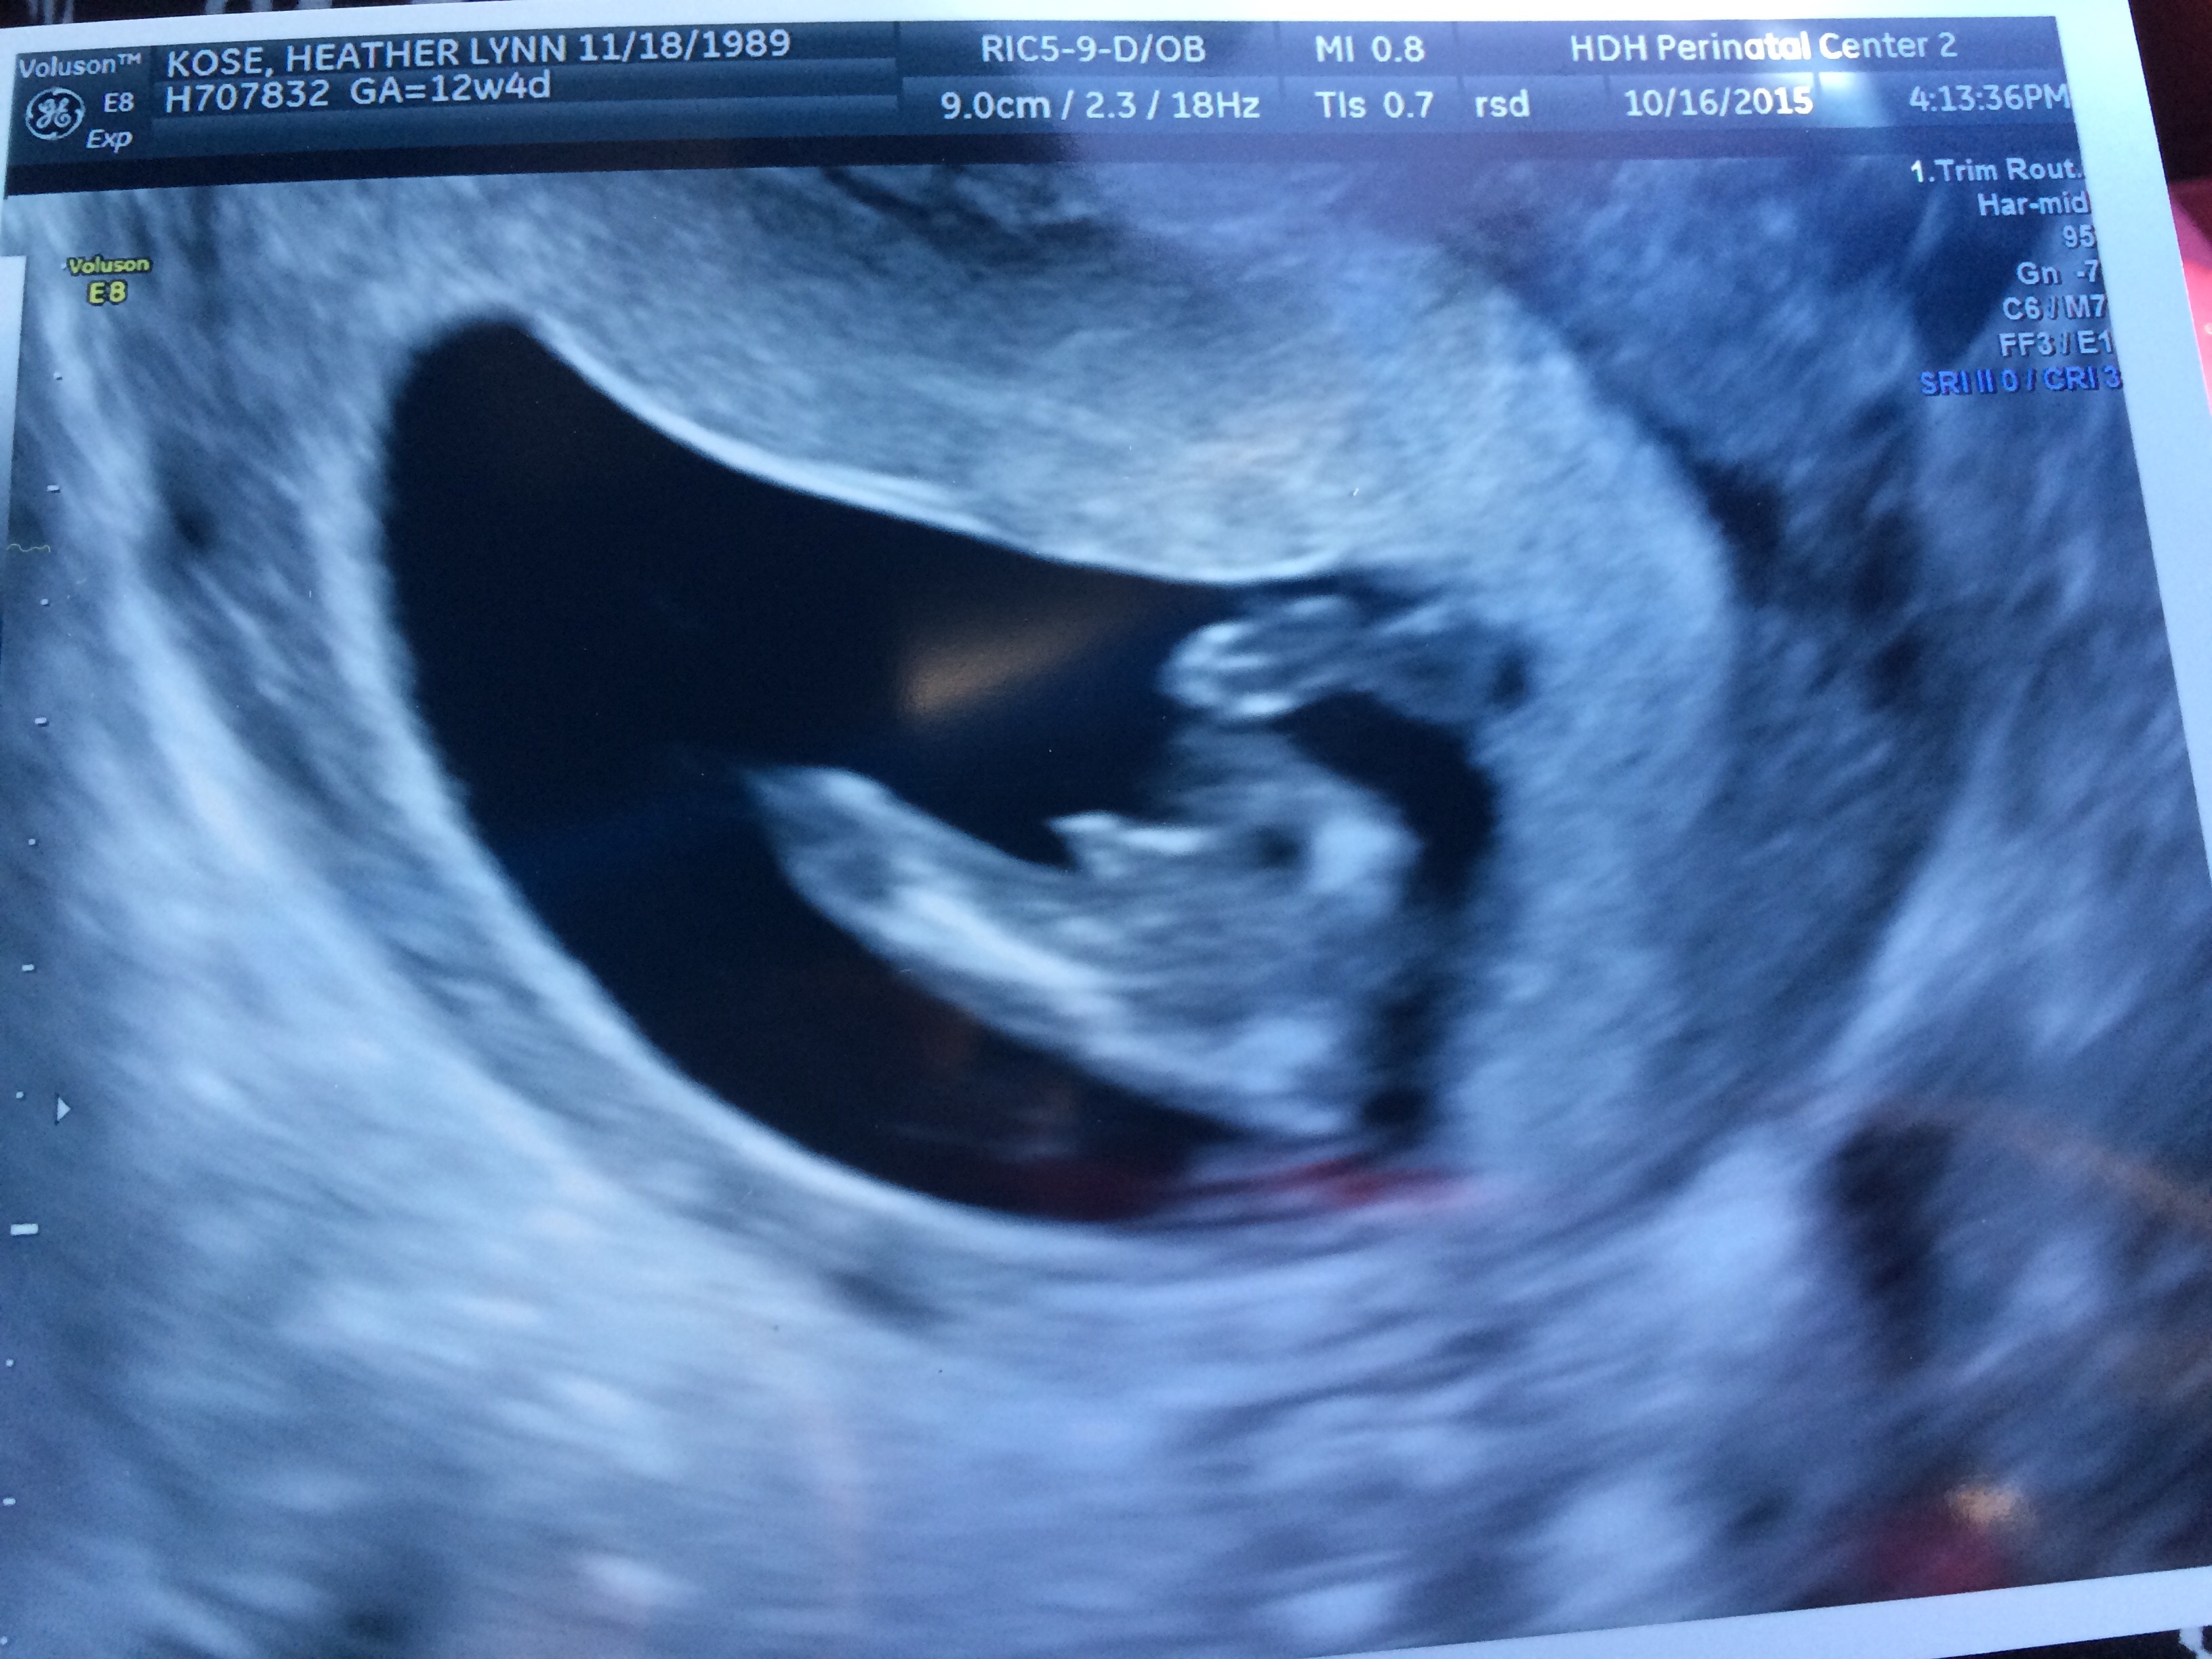

So the last week I've been so down and scared because I went to have myNT scan done and the nurse said the neck measurement was 3.1. She said it was kinda thick for me being 13 wks and 26 yrs old. So I googled and worried and couldn't sleep but got the call yesterday that my blood work is all great and I should have nothing to worry about! I just want to let any other mommies going thru that scare to not lose faith! A higher neck measurement doesn't always mean somethings wrong!! And I found out it's a boy! It's a stressful time mamas but hang in there were gonna make it thru this!